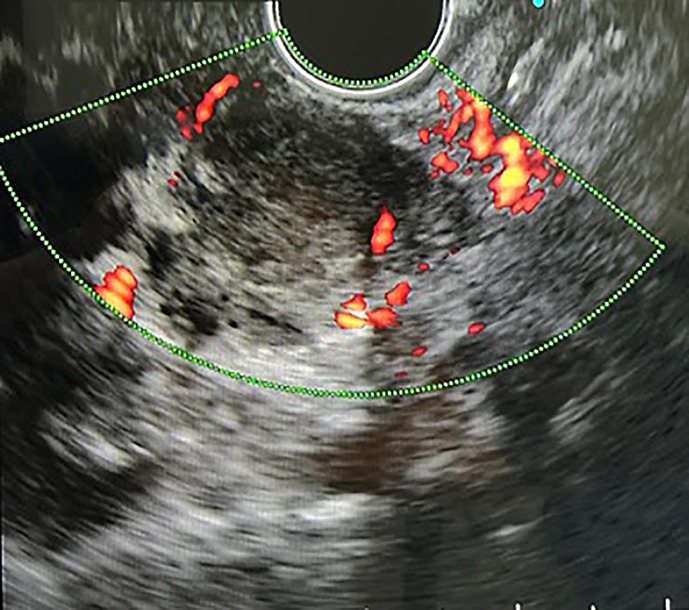

Case presentation: We found a submucosal mass with ulceration in the stomach cardia on esophagoduodenoscopy (EGD). The endoscopic ultrasound (EUS) finding was a hypoechoic submucosal lesion with a clear margin; specimens were taken using fine needle aspiration (FNA) for further histopathological examination. The result indicated granuloma of Mycobacterium Tuberculosis in pathology, suggesting that the diagnosis was gastric TB. The patient was then treated with antitubercular therapy regimen for 9 months. The previously documented mass in the stomach cardia was no longer visible on the follow-up endoscopy examination, and the patient was considered cured.

简介胃肠道结核(TB),特别是胃结核,是一种罕见的肺外结核。由于症状和体征不具特异性,诊断极具挑战性。在本病例报告中,一名 22 岁的男性因反复吐血和便血前来就诊:我们在食管十二指肠镜检查(EGD)中发现胃贲门处有一个粘膜下肿块,并伴有溃疡。内镜超声(EUS)检查发现黏膜下病变呈低回声,边缘清晰;我们用细针穿刺(FNA)取标本进行进一步组织病理学检查。病理结果显示为结核分枝杆菌肉芽肿,提示诊断为胃结核。随后,患者接受了为期 9 个月的抗结核治疗。在随访的内镜检查中,之前记录的胃贲门肿块已不复存在,患者被视为治愈:本病例表明,有胃肠道症状的患者,尤其是生活在结核病流行地区的患者,应考虑胃结核。内镜检查,如胃肠道造影(EGD)和胃超声波检查(EUS),可能有助于胃结核的诊断。